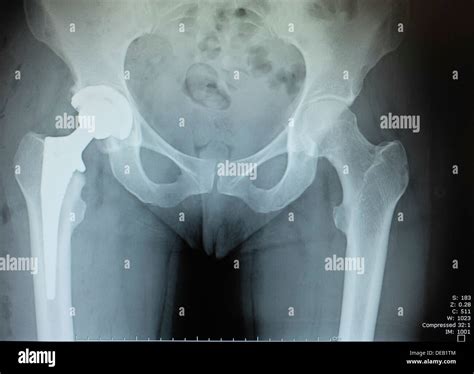

A Double Hip Replacement is a surgical procedure where both hip joints are replaced with artificial implants. This is often recommended for patients who experience severe pain and limited mobility in both hips. The procedure aims to relieve pain, improve joint function, and enhance the overall quality of life.

• Implant Placement: The artificial hip components are placed and secured in position. The femoral component is inserted into the thighbone, and the acetabular component is placed in the hip socket.